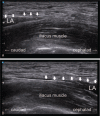

Methods: Twenty-two patients aged 70 to 90 years who underwent bipolar hemiarthroplasty for femoral neck fracture were recruited and allocated randomly into 2 groups: FICB group (n = 11) and Non-FICB group (n = 11). All patients received spinal anesthesia with 10 mg of 0.5% hyperbaric bupivacaine. After surgery, the FICB was conducted using a modified technique with 0.2% ropivacaine (40 mL) under ultrasonographic guidance, and the intravenous PCA was administered to patients in both groups in the separate block room. The PCA was set up in the only bolus mode with no continuous infusion. The visual analog scale (VAS) and the opioid consumption were noted at 4, 8, 12, 24, and 48 hours postoperatively.